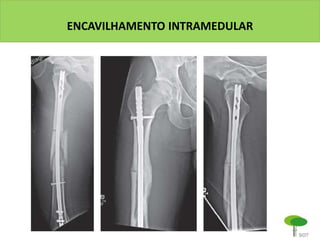

ENCAVILHAMENTO INTRAMEDULAR

É a técnica padrão para frats. diafisárias de

ossos longos

Vantagens sobre a placa:

- Acesso / exposição mais limitados

- Menor taxa de infecção

- Menor aderência / cicatriz no

quadríceps

- Menor estresse tênsil